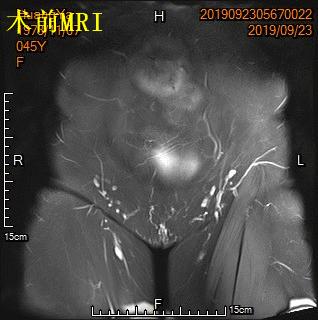

中年女性,发现子宫肌瘤进行性增大5年余。彩超提示多发、巨大子宫肌瘤,肌瘤外突明显,最大者直径近10cm。近半年尿频、尿急症状进行性加重,考虑增大的子宫肌瘤压迫膀胱所致。

- 盆腔磁共振检查显示显示多发巨大子宫肌瘤,压迫膀胱。

MRI显示多发子巨大宫肌瘤,压迫膀胱

冠状位